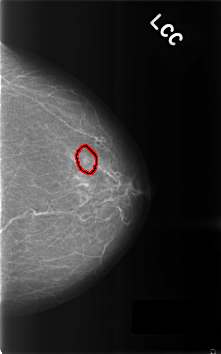

C_0303_1.LEFT_CC

LEFT_CC LINES 4592 PIXELS_PER_LINE 2872 BITS_PER_PIXEL 12 RESOLUTION 50 OVERLAY

FILE: C_0303_1.LEFT_CC.OVERLAY

TOTAL_ABNORMALITIES 1

ABNORMALITY 1

LESION_TYPE MASS SHAPE LOBULATED MARGINS CIRCUMSCRIBED

ASSESSMENT 3

SUBTLETY 4

PATHOLOGY BENIGN

TOTAL_OUTLINES 1

BOUNDARY